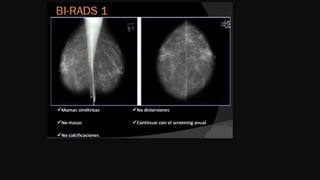

Motivo del estudio Descripcióndel tejido predominante Hallazgos Categorización Conclusión Recomendación Reporte mamográfico Breast Imaging Report And Data System

• 64.

Reporte mamográfico Parénquima mamario BreastImaging Report And Data System Tejido predominante: lipomatoso,escaso tejido glandular Tejido fibroglandular moderado. Tejido fibroglandular abundante. (mamas densas)

categorización Reporte mamográfico BreastImaging Report And Data System